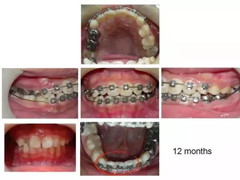

下颌的前牙部分四颗门牙大小不一,乳牙的形态、宽度跟恒牙都不一样,如果不考虑生长发育直接排齐牙齿会增加将来的种植难度,现有的宽度来说,种一颗间隙太大,种两颗太拥挤。操作中,把下颌牙齿用弹簧箍推开,有一定缝隙产生后用填补蛀牙的树脂材料将牙齿堆叠成与左右牙齿一样的宽度。乳牙部分并没有加箍,后面磨牙部分如果咬合关系正常无需移动。

经过一段时间,缺恒牙的乳牙还是会掉。到4-5年后,先天缺失的乳牙开始脱落。此时修改维持器一方面作为空间维持器,一方面用做假牙的材料堆叠做成类似活动假牙。